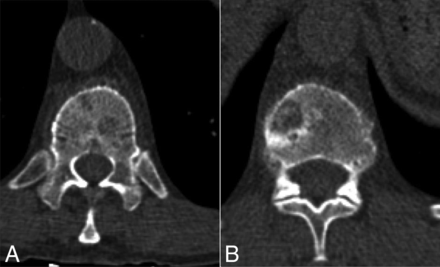

On the basis of cross-sectional CT imaging, lesions were classified into 65 lytic, 13 sclerotic, and 24 mixed lytic/sclerotic. The tumor area ranged between 0.75 to 15.0 cm2 (mean, 3.6 ± 2.2 cm2) based on CT and MR imaging review by the interventional radiologist. Figure 1 demonstrates an example of a lytic osseous metastasis in a patient with metastatic breast carcinoma.

Axial CT images with the patient supine demonstrate lytic osseous metastasis in the T11 (A) and T12 (B) vertebral bodies in a 60-year-old woman with metastatic breast carcinoma.